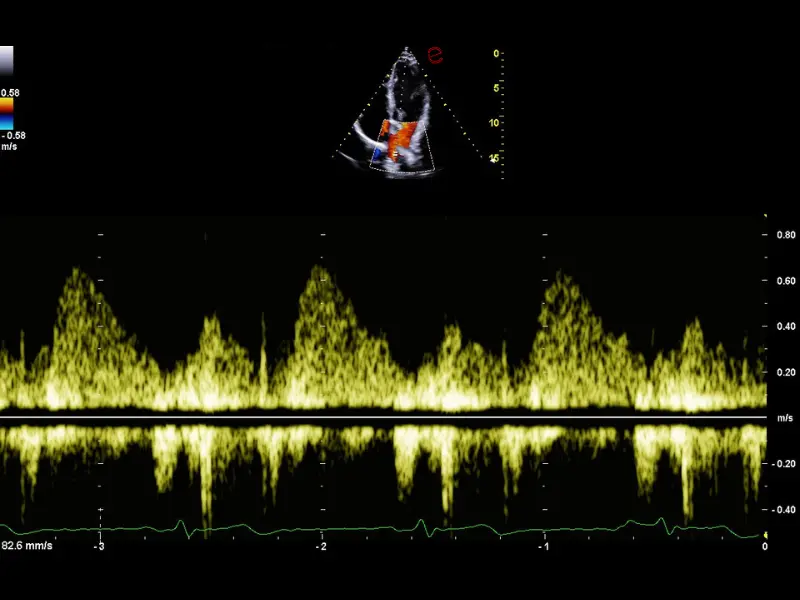

MyLab™C30 - Polm - Doppler

MyLab™C30 - Polm - Doppler